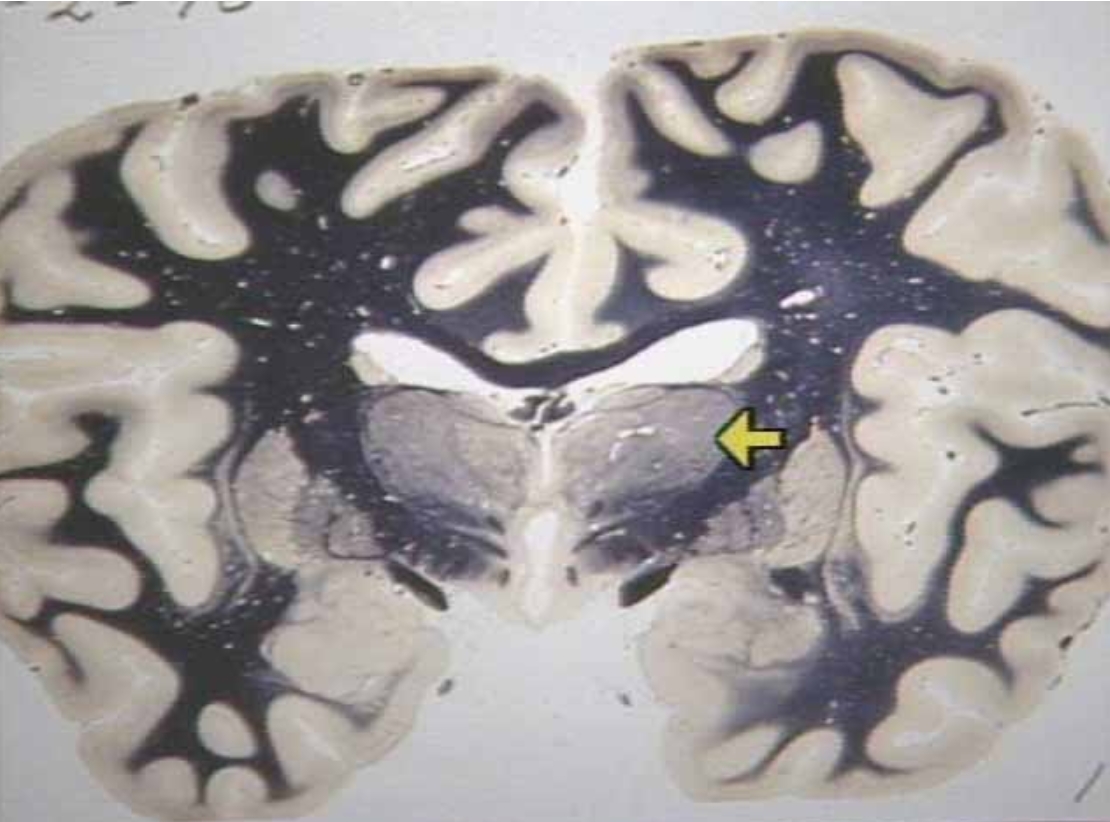

What is the arrow pointing at?

Posterior Commissure (arrow)